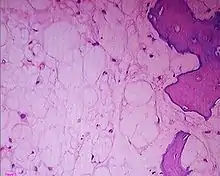

Histologic Subtypes

- Conventional

- Chondroid

- Better prognosis

- Subtype with predilection for skull base location

- Dedifferentiated